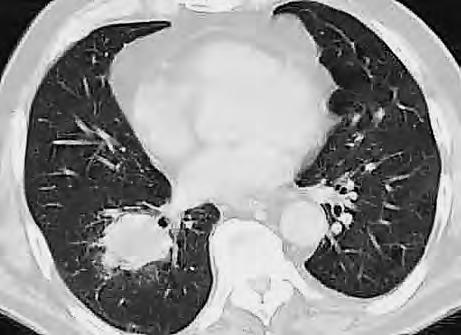

Diferenciální diagnóza

Expanzivní ložisko vCNS může být někdy způsobeno benigním patologickým procesem (abscesem, kavernomem, meningeomem), ale může jít také ometastázu známého nebo doposud ukrytého tumoru, viz obr. 1.4 a1.5. Do mozku často metastazují následující tumory: bronchogenní karcinom, obzvláště jeho malobuněčná varianta, karcinomy prsu aledvin. V80 %případů jsou tyto metastázy uloženy supratentoriálně.

Metastázy mohou vCNS vytvořit jak solitární, tak ivícečetná ložiska, mohou však také infiltrovat meningy (bronchogenní karcinom, karcinomy prsu ižaludku).